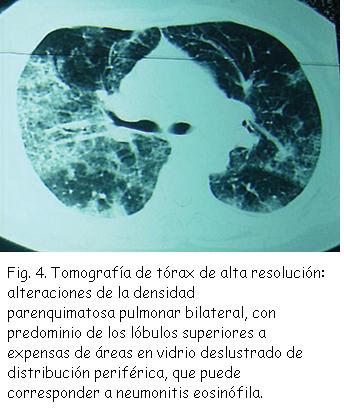

Tomografía de tórax de alta resolución: alteraciones de la densidad parenquimatosa pulmonar bilateral, con predominio de los lóbulos superiores a expensas de áreas en vidrio deslustrado de distribución periférica, que puede corresponder a neumonitis eosinófila. Derrame pleural bilateral. Adenopatías paratraqueales (Figura 4). Abdomen y pelvis: normales.